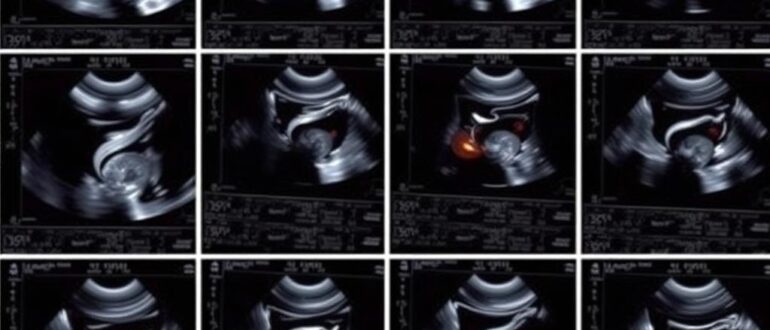

Современная пренатальная диагностика держится на перекрестке техники, науки и человеческой ответственности. Электронные руководства становятся не просто пособиями, а навигаторами, которые помогают врачам и будущим родителям ориентироваться в массиве

В современном здравоохранении информация перестала быть редким ресурсом — она стала доступной и немедленной. Но когда речь заходит о перинатологии и ведении беременности высокого риска, скорость и точность

Современная медицина все больше опирается на единые стандарты, структурированные данные и прозрачные процессы. Онлайн‑сборники протоколов УЗИ внутренних органов — это инструмент, который переводит в цифру и шаблоны годами